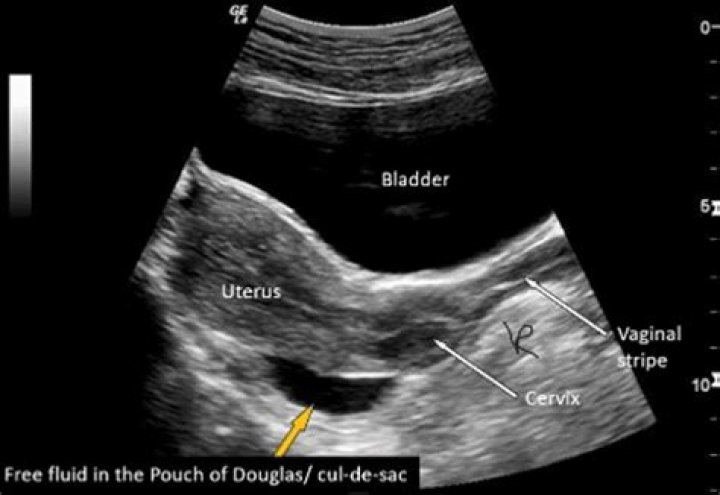

The Pouch of Douglas is an anatomical structure located in the female pelvis, specifically between the rectum and the posterior wall of the uterus. It is part of the peritoneal cavity and serves as a potential space that can accumulate fluid in certain pathological conditions. Understanding its location and function is essential for healthcare providers when interpreting ultrasound images.

This anatomical structure is named after Dr. James Douglas, a Scottish anatomist who first described it. Its position makes it a critical point of focus during pelvic ultrasound examinations, particularly in cases involving fluid accumulation or mass detection.

The Pouch of Douglas holds significant clinical importance due to its role in various gynecological conditions. Its anatomical position makes it a common site for fluid accumulation, which can indicate underlying pathologies such as endometriosis, pelvic inflammatory disease, or ovarian cysts. Recognizing these conditions early through ultrasound can lead to timely interventions and improved patient outcomes.

Ultrasound plays a pivotal role in diagnosing various conditions associated with the Pouch of Douglas. By providing detailed images of the pelvic structures, ultrasound can help identify fluid accumulation, masses, and other abnormalities. This section will discuss some of the most common conditions detected using this technology.